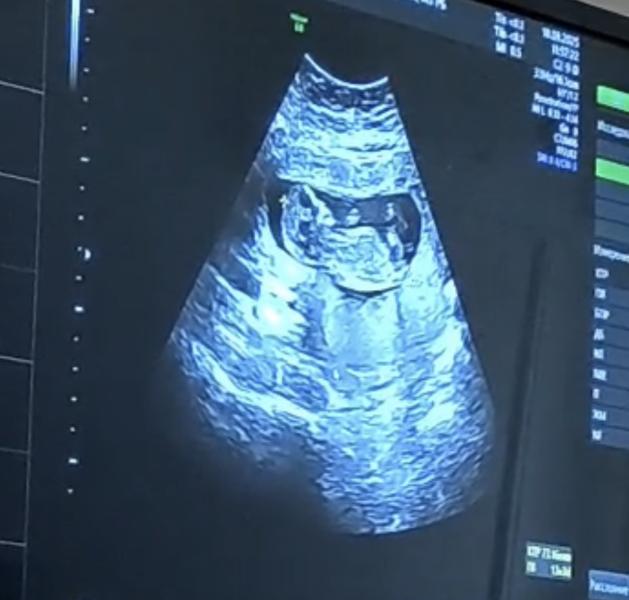

Прошла 1 скрининг🤞🏻Самый быстрый из всех😅две минуты осмотр😁Ну всезнающие мои кто там будет у меня 😌😁

Думаю, что мальчик)))

Плохо видно (( ну если учесть, что это не нога а тот самый бугорок то смею предположить, что будет мальчик